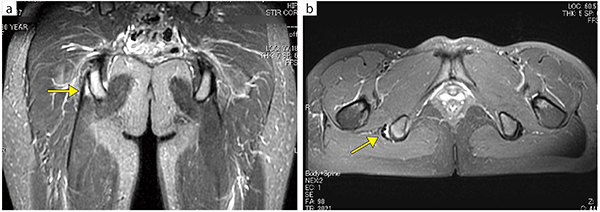

■症例1:ハムストリング総腱の不全剥離

30歳,女性,フットサル選手。右坐骨結節ハムストリング腱付着部の不全剝離損傷と診断。

a:SSTIR coronal,TR/TE/FA:3960/40,80/90°,FOV:370mm,スライス厚:5mm

b:PDWI FatSat axial,TR/TE/FA:3021/36/90°,FOV:350mm,スライス厚:5mm